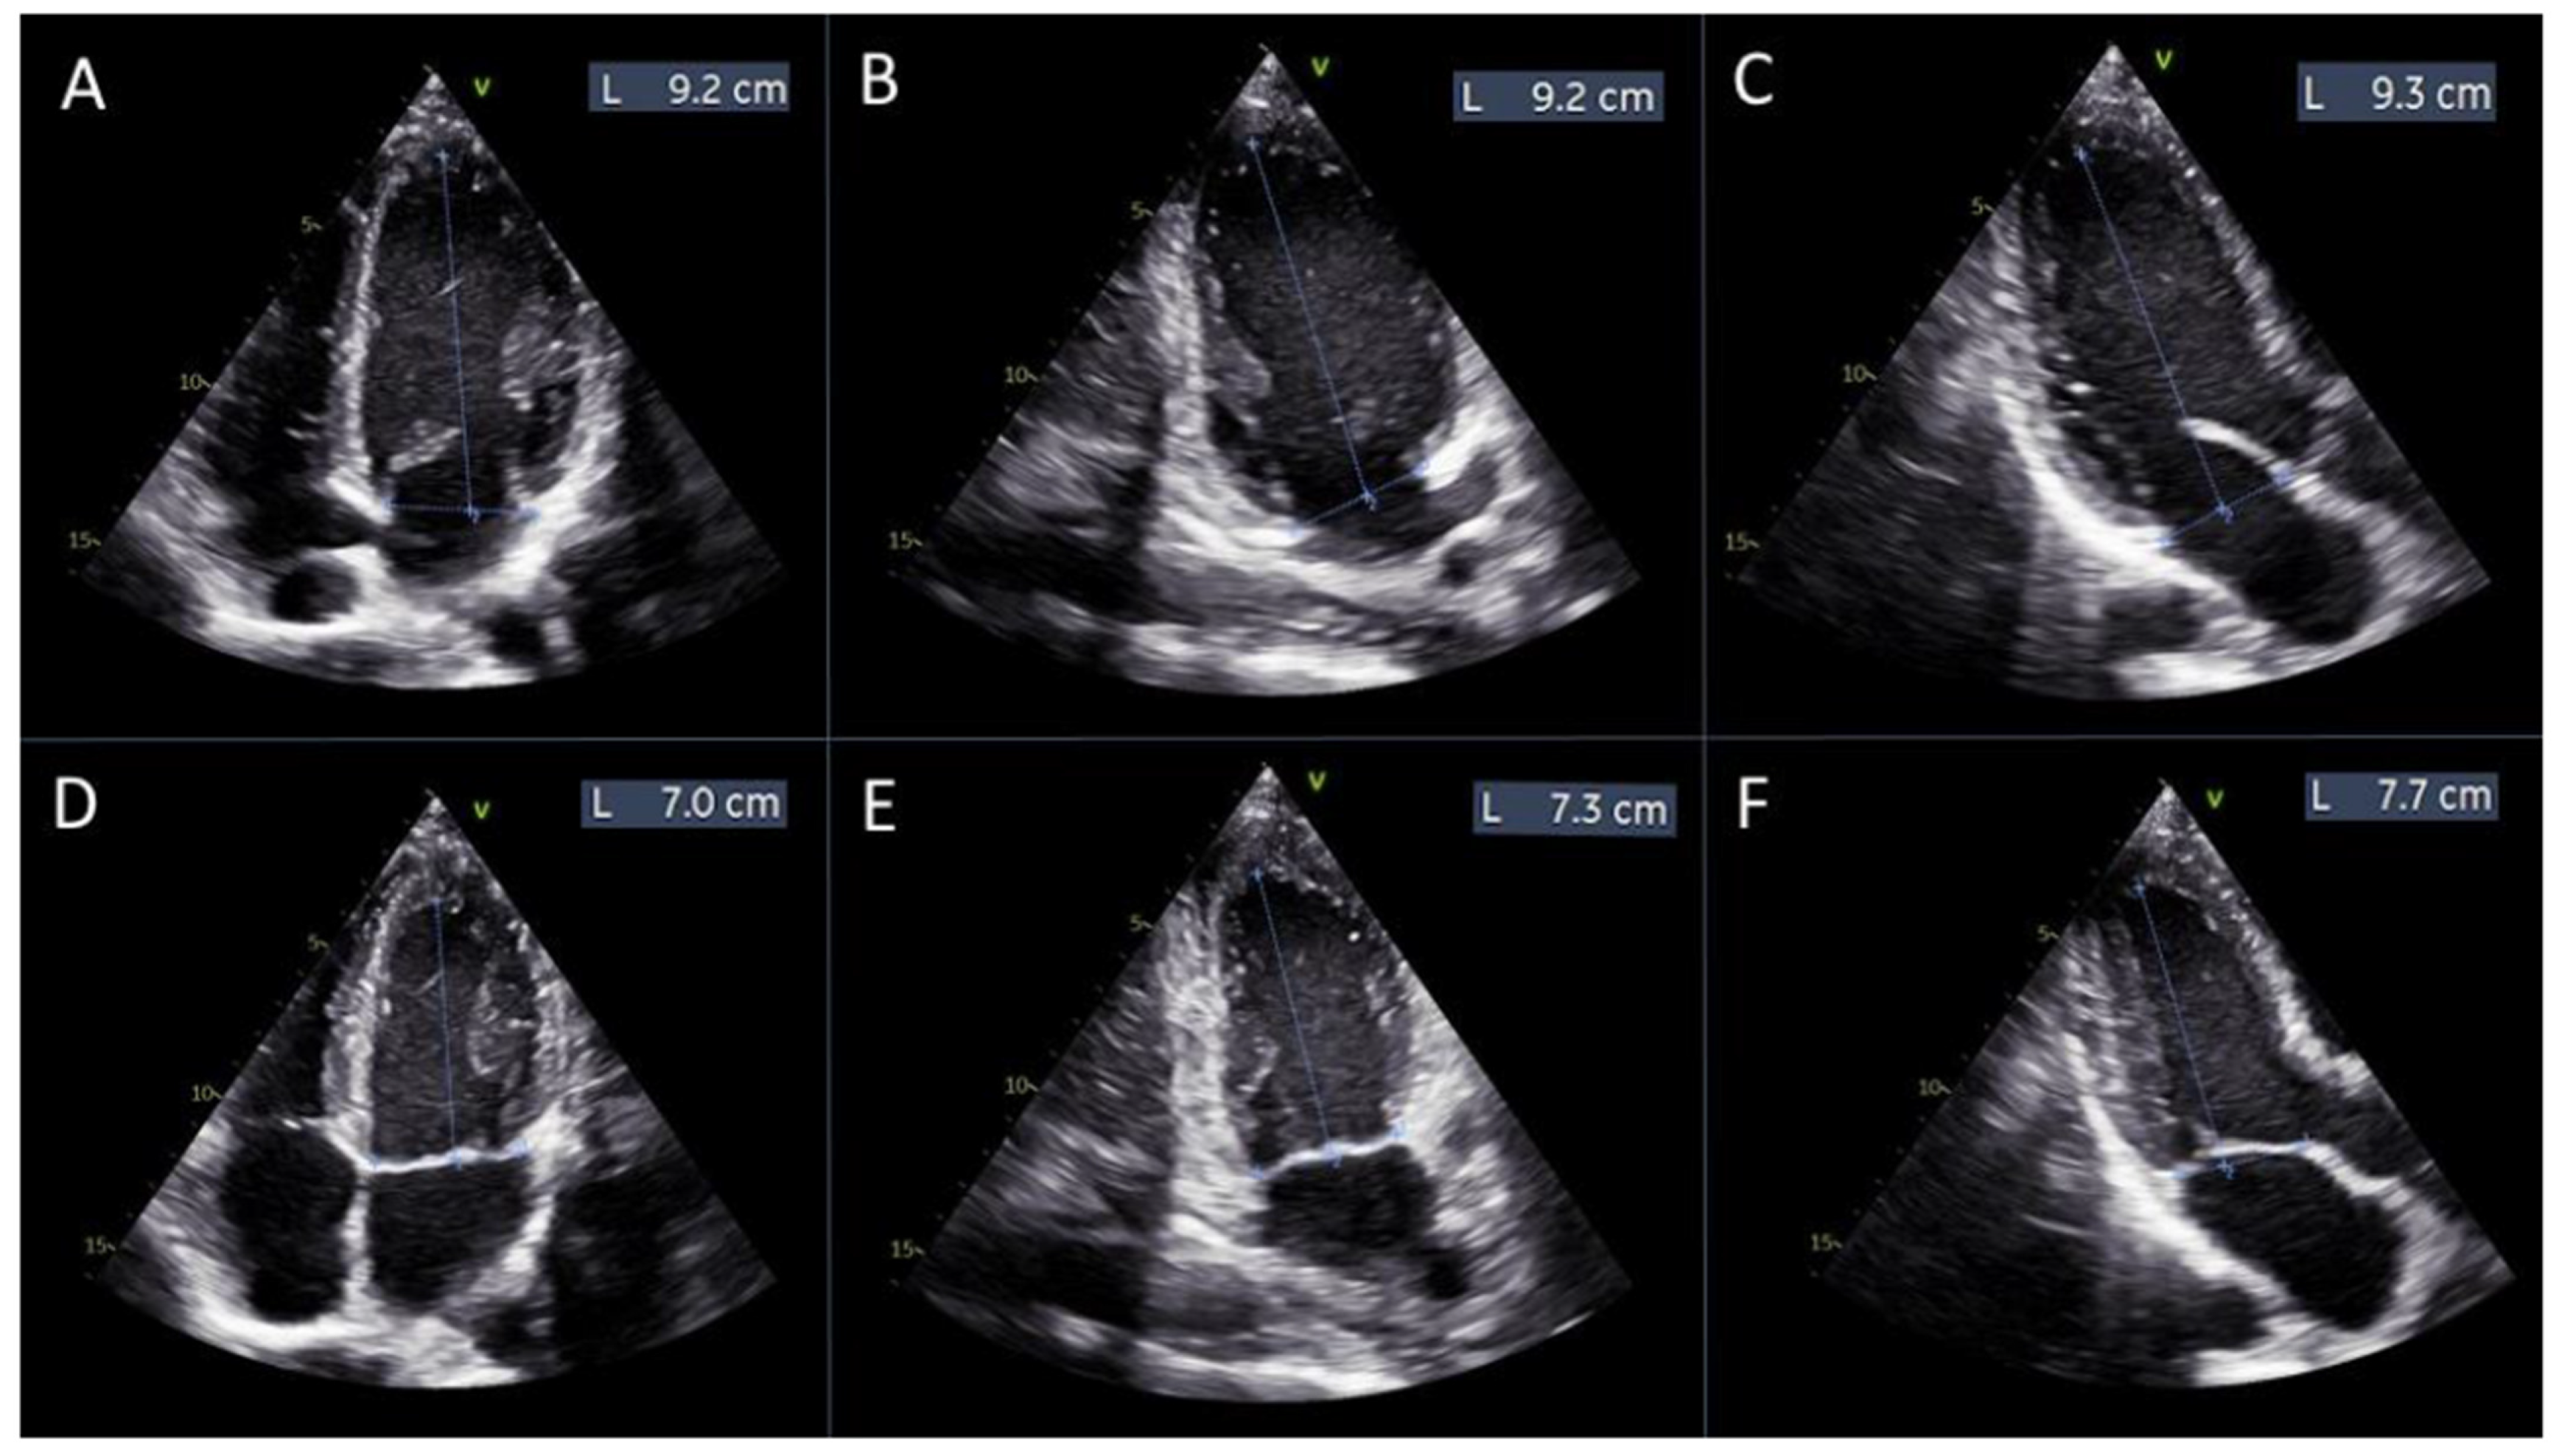

where L1d, L2d, and L3d are the distances from the mitral annulus plane to the apex of the left ventricle in diastole, measured in the 4-chamber, 2-chamber, and 3-chamber views, respectively (Figure 2A–C).

Figure 2.

Measurements of left ventricular length for manual global longitudinal strain calculation. Panels (A–C) display the measurements of the left ventricular length obtained from the apical 4-chamber, 2-chamber, and 3-chamber views, respectively, at diastole. Panels (D–F) show the corresponding measurements from the same apical views at systole.

L1s, L2s, and L3s are the distances from the mitral annulus plane to the apex of the left ventricle in systole, measured in the same views (Figure 2D–F).